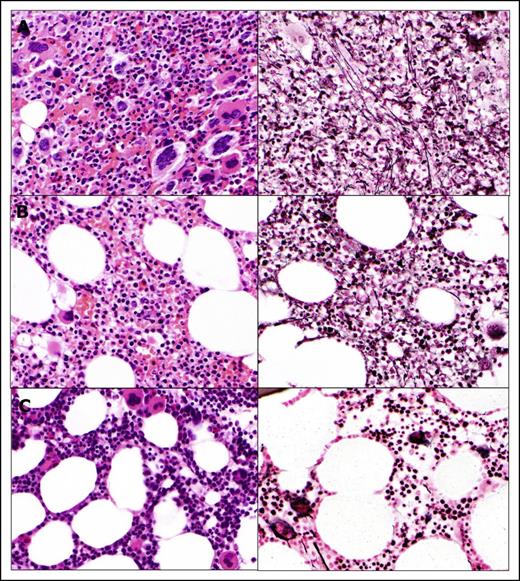

Rapid clinical improvement was followed by a complete hematologic remission within first 12 months, characterized by resolution of leukocytosis by the first month, disappearance of peripheral blasts by the second month, and normalization of peripheral blood smear by the 12th month. The JAK2 allele burden decreased steadily with time and remained undetectable after 77 months on therapy along with the IDH2 mutation, which was also undetectable (complete molecular response) (Figure 1C). Deletion 20q was repeatedly detected along with trisomy 8, which was acquired at a later time point; however, after 72 months, only a normal diploid karyotype was present. Bone marrow improvement was slowly observed over time (Figure 2). At the pretrial assessment (Figure 2A), a 100% cellular bone marrow contained hyperplastic, clustered megakaryocytes with abnormal chromatin clumping and hyperchromatic nuclei, and diffuse, dense reticulin fibrosis with many intersections. After 24 months of therapy (Figure 2B), the bone marrow cellularity had returned to normal (40%) with some features of dyshemopoiesis and occasional atypical megakaryocytes. No blasts were detected, and the reticulin fibers were less prominent, though still present as patches of dense reticulin. After 88 months on therapy (Figure 2C), the bone marrow remained normocellular, with all cells showing normal morphology, restored trilineage hemopoiesis, and complete disappearance of the reticulin fiber patterns (MF-0), confirming a complete bone marrow remission. Hematopoiesis was polyclonal, as assessed by the human androgen receptor X-chromosome inactivation assay (supplemental Figure 1).14

Histomorphologic assessment of bone marrow core biopsy samples. (A) Bone marrow before therapy. Bone marrow after 24 months (B) and after 88 months (C) on therapy. Hematoxylin and eosin staining, original magnification ×500.